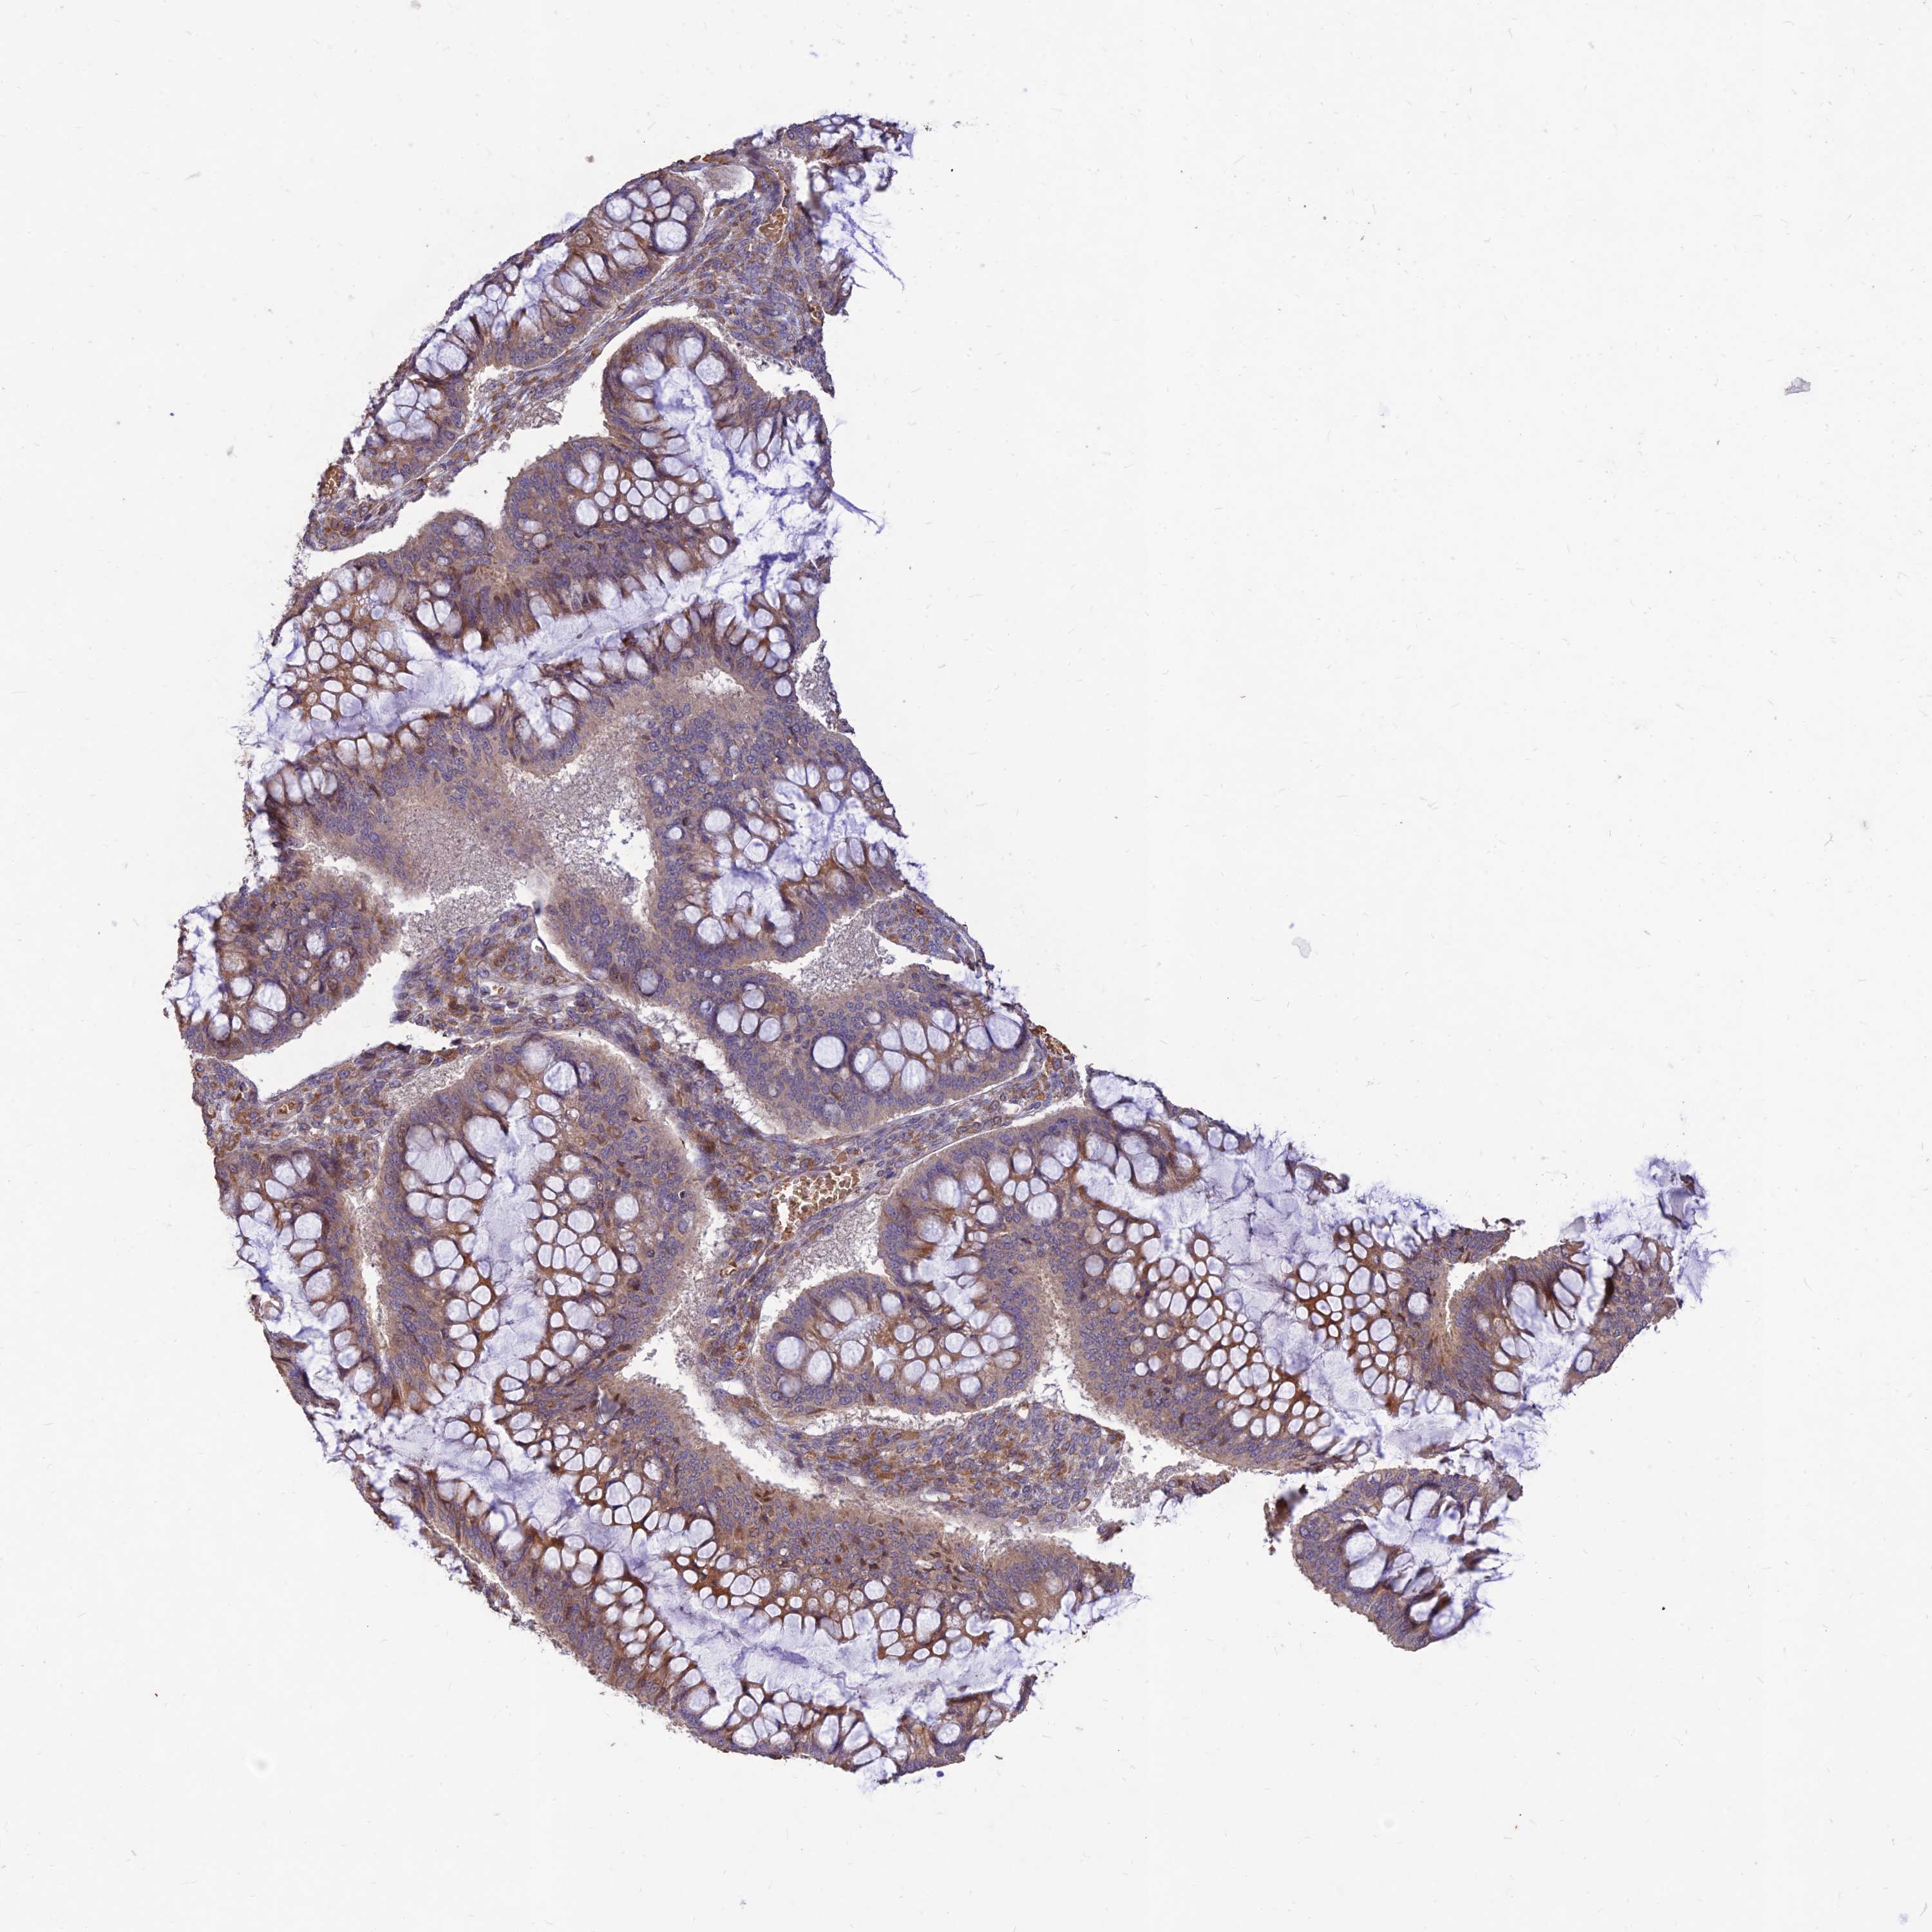

OVARIAN CANCER - Protein expressioni

A mouse-over function shows sample information and annotation data. Click on an image to view it in a full screen mode. Samples can be filtered based on level of antibody staining by selecting one or several of the following categories: high, medium, low and not detected. The assay and annotation is described here.

Note that samples used for immunohistochemistry by the Human Protein Atlas do not correspond to samples in the TCGA dataset.

Antibody stainingi

Antibody staining in the annotated cell types in the current human tissue is reported as not detected, low, medium, or high, based on conventional immunohistochemistry profiling in selected tissues. This score is based on the combination of the staining intensity and fraction of stained cells.

Each image is clickable and will lead to virtual microscopy that enables deeper exploration of all samples and also displays staining intensity scores, fraction scores and subcellular localization as well as patient and tissue information for each sample.

Antibody HPA043266

Staining

High

Medium

Low

Not detected

Intensity

Strong

Moderate

Weak

Negative

Quantity

>75%

75%-25%

<25%

None

Location

Nuclear

Cytoplasmic/membranous

Cytoplasmic/membranous,nuclear

Cystadenocarcinoma, serous, NOS

Carcinoma, NOS

Cystadenocarcinoma, mucinous, NOS

Carcinoma, endometroid